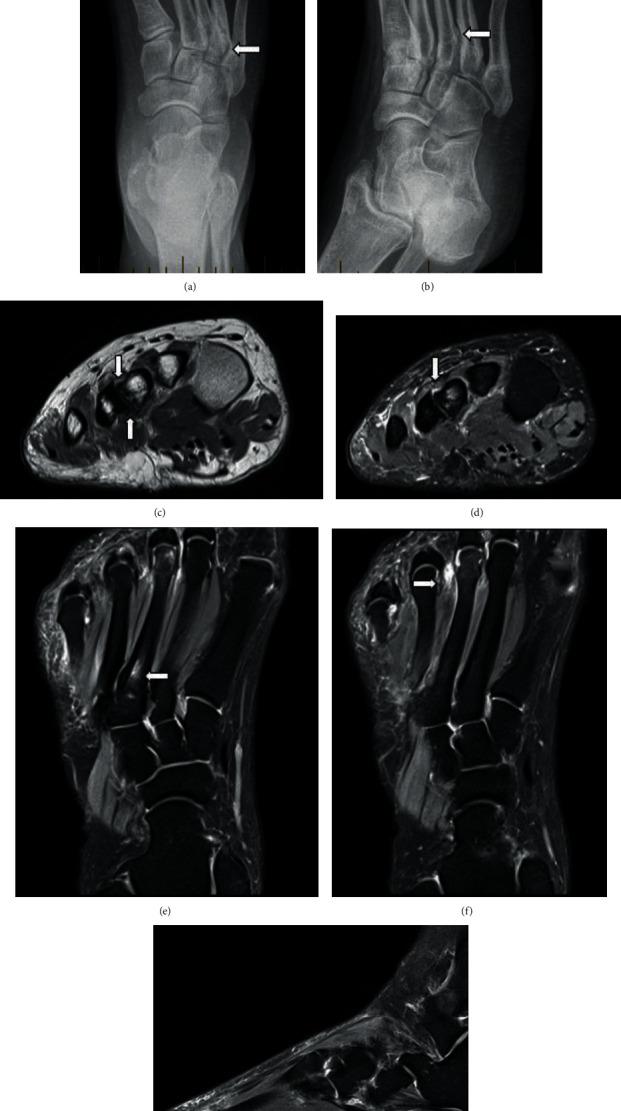

Coalition is defined as abnormal bridging between two bones, and the connection can be osseous or nonosseous. Most coalitions in the foot involve the hindfoot. Intermetatarsal coalition is thought to be much rarer than the more common hindfoot coalitions and has only been reported sporadically in the orthopedic literature. We present two patients with nonosseous intermetatarsal coalition presenting with nonspecific dorsolateral foot pain and describe the imaging findings of intermetatarsal coalition with different modalities. We suspect that whilst rarely described, intermetatarsal coalition is quite likely a more common underrecognized entity than a rare entity. This report is aimed at increasing the awareness of coalition in this location, in the radiology community, particularly the nonosseous ones, given that this condition can be debilitating but treatable.

联合被定义为两块骨头之间的异常连接,这种连接可以是骨性的或非骨性的。足部的大多数联合发生在后足。跖骨间联合被认为比更常见的后足联合要罕见得多,在骨科文献中仅有零星报道。我们报告了两名患有非骨性跖骨间联合且表现为足部背外侧非特异性疼痛的患者,并描述了不同影像学检查方式下跖骨间联合的表现。我们怀疑,虽然跖骨间联合很少被描述,但它很可能是一种比罕见病更常见却未被充分认识的病症。鉴于这种情况可能使人衰弱但可治疗,本报告旨在提高放射学界对该部位联合,尤其是非骨性联合的认识。